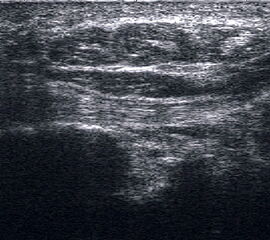

Tenosynovialitis

Eine Tenosynovialitis, hier im Bereich des Os metatarsale I stellt sich als echoarmer Ring (Flüssigkeit) um die echoreiche Sehne dar.

Abbildung 50

Lagerung: Rückenlage.

Schnittführung: Ventraler LS und TS über dem OSG, hinter dem Innen- bzw. Außenknöchel und den Metatarsalia.

Referenzstrukturen: In Abhängigkeit von der Lokalisation Innenknöchel, Fibulaspitze, dorsaler Mittelfuß, Sehnen.

Befunde: Ein echoarmer Ring um die echogene Sehne ist Ausdruck der Flüssigkeitsumscheidung. Bei entzündlicher Ursache auf dem Boden einer rheumatologischen Erkrankung kommt es im zeitlichen Verlauf zum Übergang in eine chronische Tendinopathie. Durch Verklebungen mit dem Sehnengleitgewebe kann das Gleiten der Sehne behindert sein.